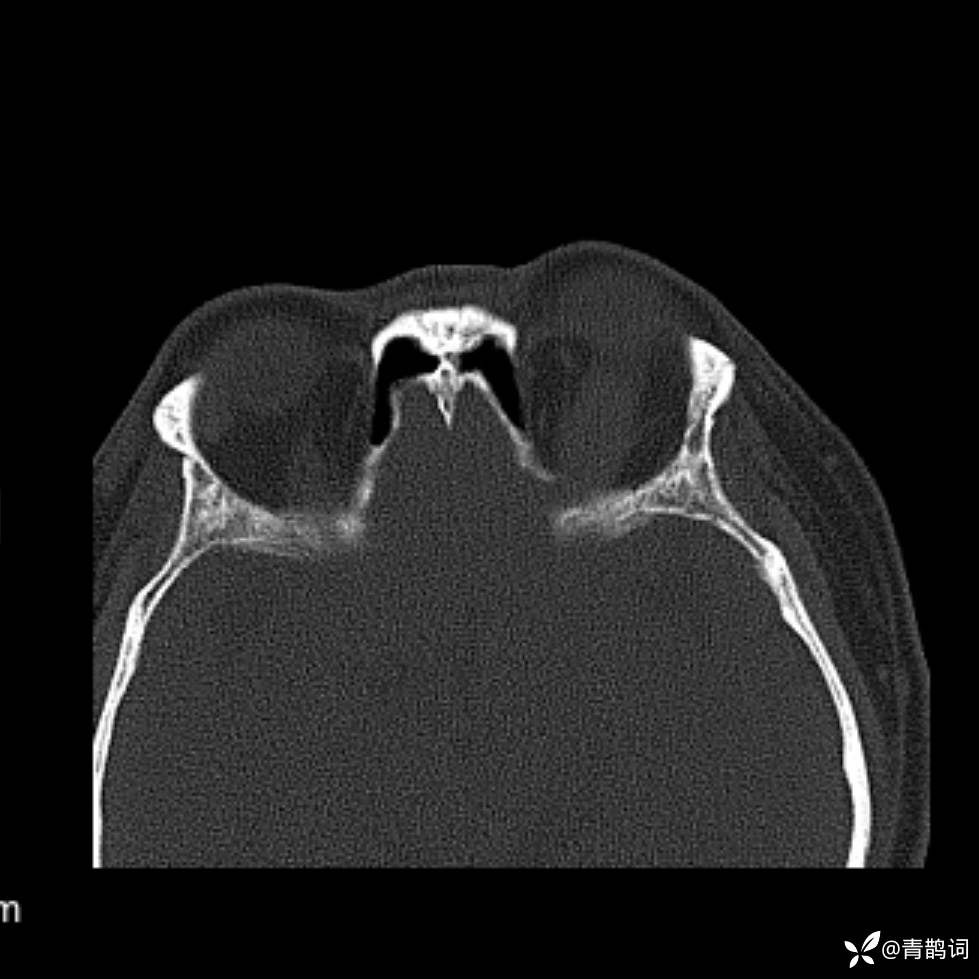

患者年龄:30岁。

患者性别:男。

简要病史:左颜面部肿胀2年,反复咳嗽咳痰,逐渐加重。

结合病史及影像学表现,期待评论区各位老师各抒己见~